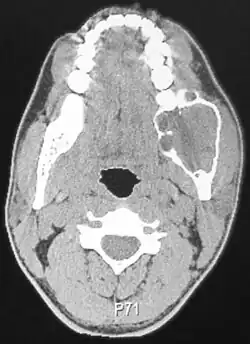

| Ameloblastoma of the mandible | |

Radiographically, the tumour area appears as a rounded and well-defined lucency in the bone with varying size and features. Numerous cyst-like radiolucent areas can be seen in larger tumours (multi-locular) giving a characteristic "soap bubble" appearance. A single radiolucent area can be seen in smaller tumours (unilocular).[8] The radiodensity of an ameloblastoma is about 30 Hounsfield units, which is about the same as keratocystic odontogenic tumours. However, ameloblastomas show more bone expansion and seldom show high density areas.[15]

Lingual plate expansion is helpful in diagnosing ameloblastoma as cysts rarely do this. Resorption of roots of involved teeth can be seen in some cases, but is not unique to ameloblastoma.[10]